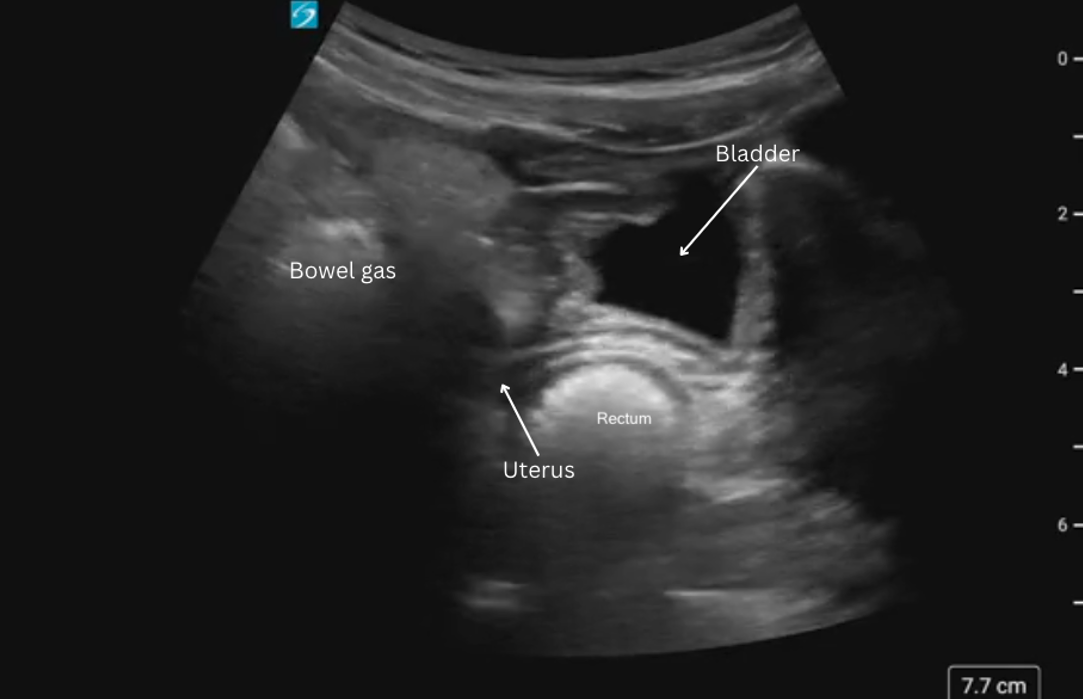

Position

The bladder sits in the pelvis just posterior to the pubic symphysis. Its size and position relevant to other structures varies according to bladder fullness.

> Full Bladder:

– Sits anterior to the uterus in females (figure 7a, 9a)

> Partially filled:

– Sits lower in the pelvis, appearing caudal to the uterus (figure 8)

– Anterior to the rectum (figure 8)

Figure 8: Sagittal view of bladder sonoanatomy in a female patient with a near empty bladder.